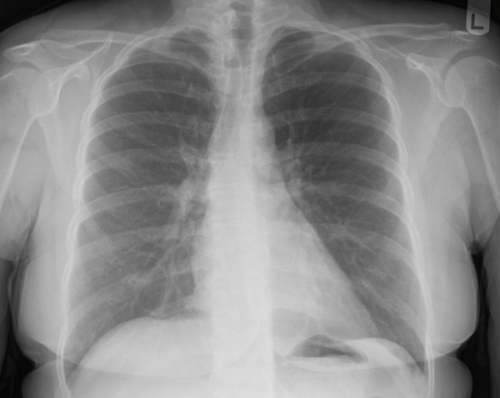

Tool to train medical student's eyes as to what a normal chest x-ray looks like, with over 500 consecutive normal images.